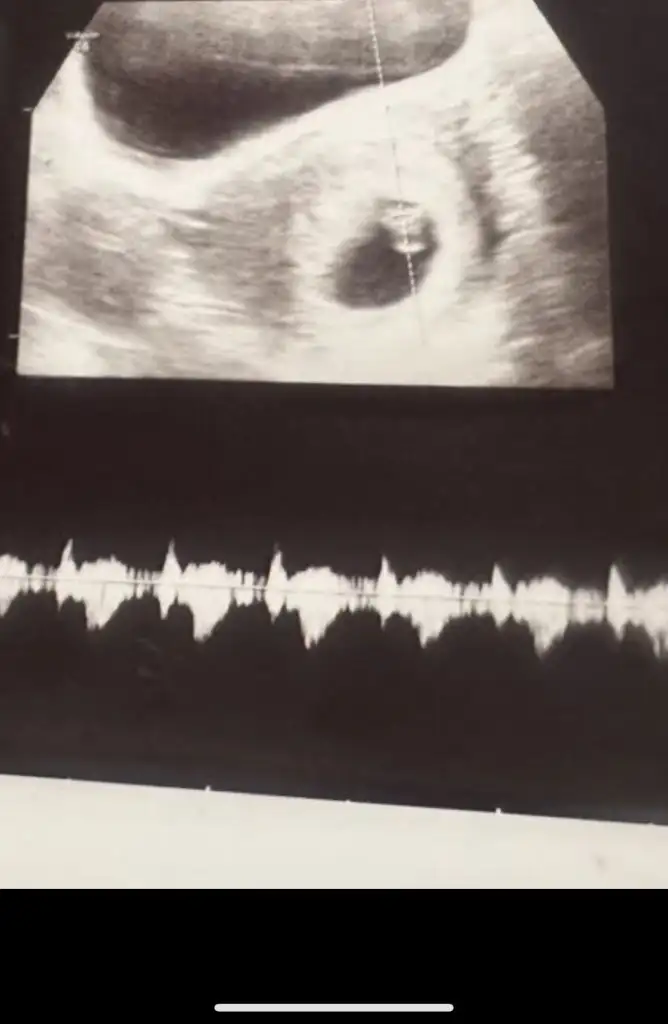

Merhaba bu 6+4 kenki görüntüsü kız gibi mi

Bu da 9+3 kenki görüntüsü. Sanki konumu değişmiş gibi değil mi?